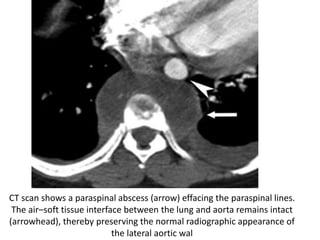

CT scan shows a paraspinal abscess (arrow) effacing the paraspinal lines.

The air–soft tissue interface between the lung and aorta remains intact

(arrowhead), thereby preserving the normal radiographic appearance of

the lateral aortic wal